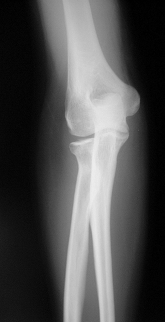

図1 a 初診時レントゲン正面像 図1 b 初診時レントゲン斜位像